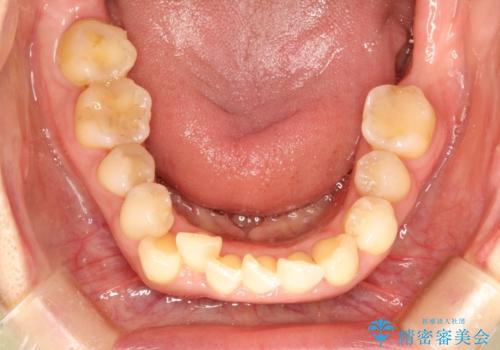

- 右上の八重歯(犬歯の突出)と、それに伴う歯並びのがたつきを主訴にご来院されました。精密検査の結果、八重歯を正しい位置に収めるためのスペースが大幅に不足していることが分かりました。

今回の治療では、右上5番の抜歯スペースを活用して八重歯(3番)を後方へ誘導しました。

インビザライン独自の3Dシミュレーションに基づき、必要な歯だけをピンポイントで動かすことで、抜歯を伴う大きな移動も効率的に行いました。

治療の結果、突出していた八重歯はきれいなアーチに収まり、左右対称でバランスの取れた口元になりました。インビザラインは自由に取り外しができるため、治療期間中も口腔内を清潔に保ちやすく、患者様もストレスなく治療を完了されました。